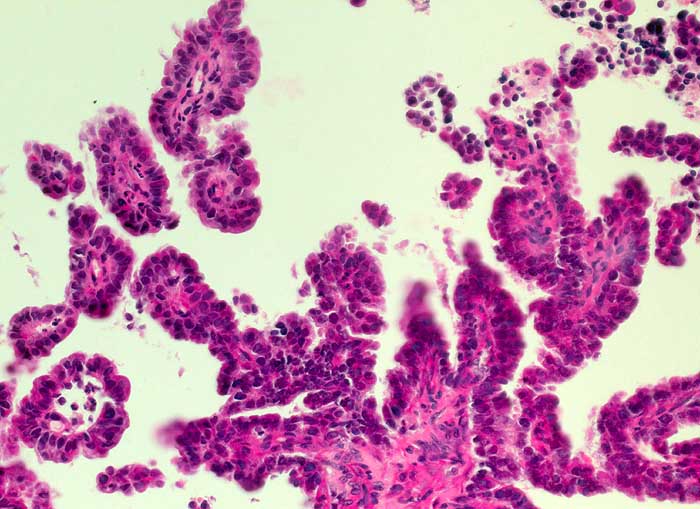

Die Zellkerne der serösen Adenokarzinome sind in den meisten Fällen hochgradig atypisch. Das Zellbild gleicht entsprechend demjenigen eines wenig differenzierten endometrioiden Adenokarzinoms. Da das seröse Karzinom anders als das endometrioide Karzinom nicht Folge eines Hyperöstrogenismus ist, zeigen die meist postmenopausalen Patientinnen keinen hohen Aufbau des Vaginalepithels im PC-Abstrich.